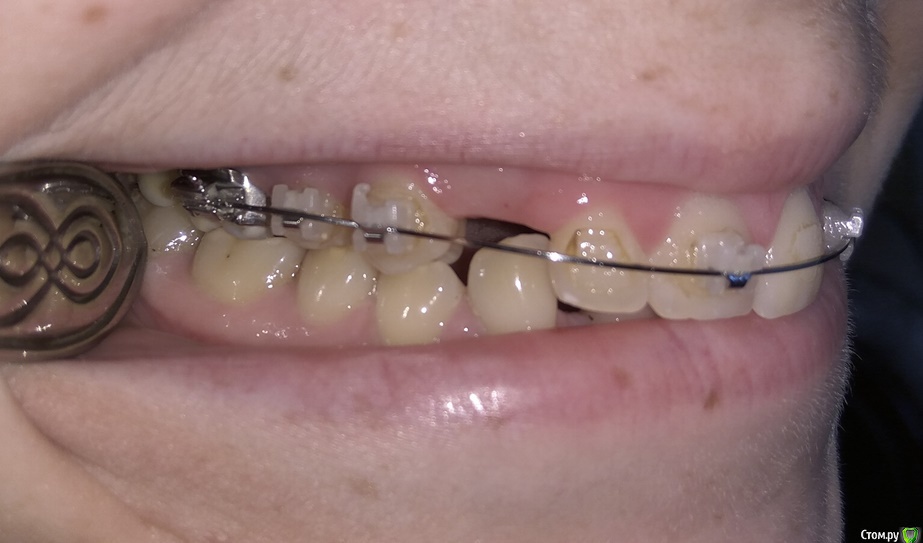

Добрый день. Уважаемые специалисты, прошу совета, БС была установлена в 2015 году, тогда же удалены молочные клыки, ортодонт сказал, что можно вытянуть, но как оказалось не все это могут сделать. Был сделан доступ к постоянным клыкам с небной стороны, приклеены кнопки, установлены лигатуры в области первых премоляров. В 2015-2016 была беременность. Примерно в феврале 2017 лигатуры были заменены на микроимплантаты в области первого моляра с небной стороны и установлены металлические лигатуры. В итоге - движение не наблюдается. Вопрос - можно ли еще пробовать их вытянуть или же делать радикально - удаление и имплантация, или после удаления можно сместить премоляры и моляры вперед?